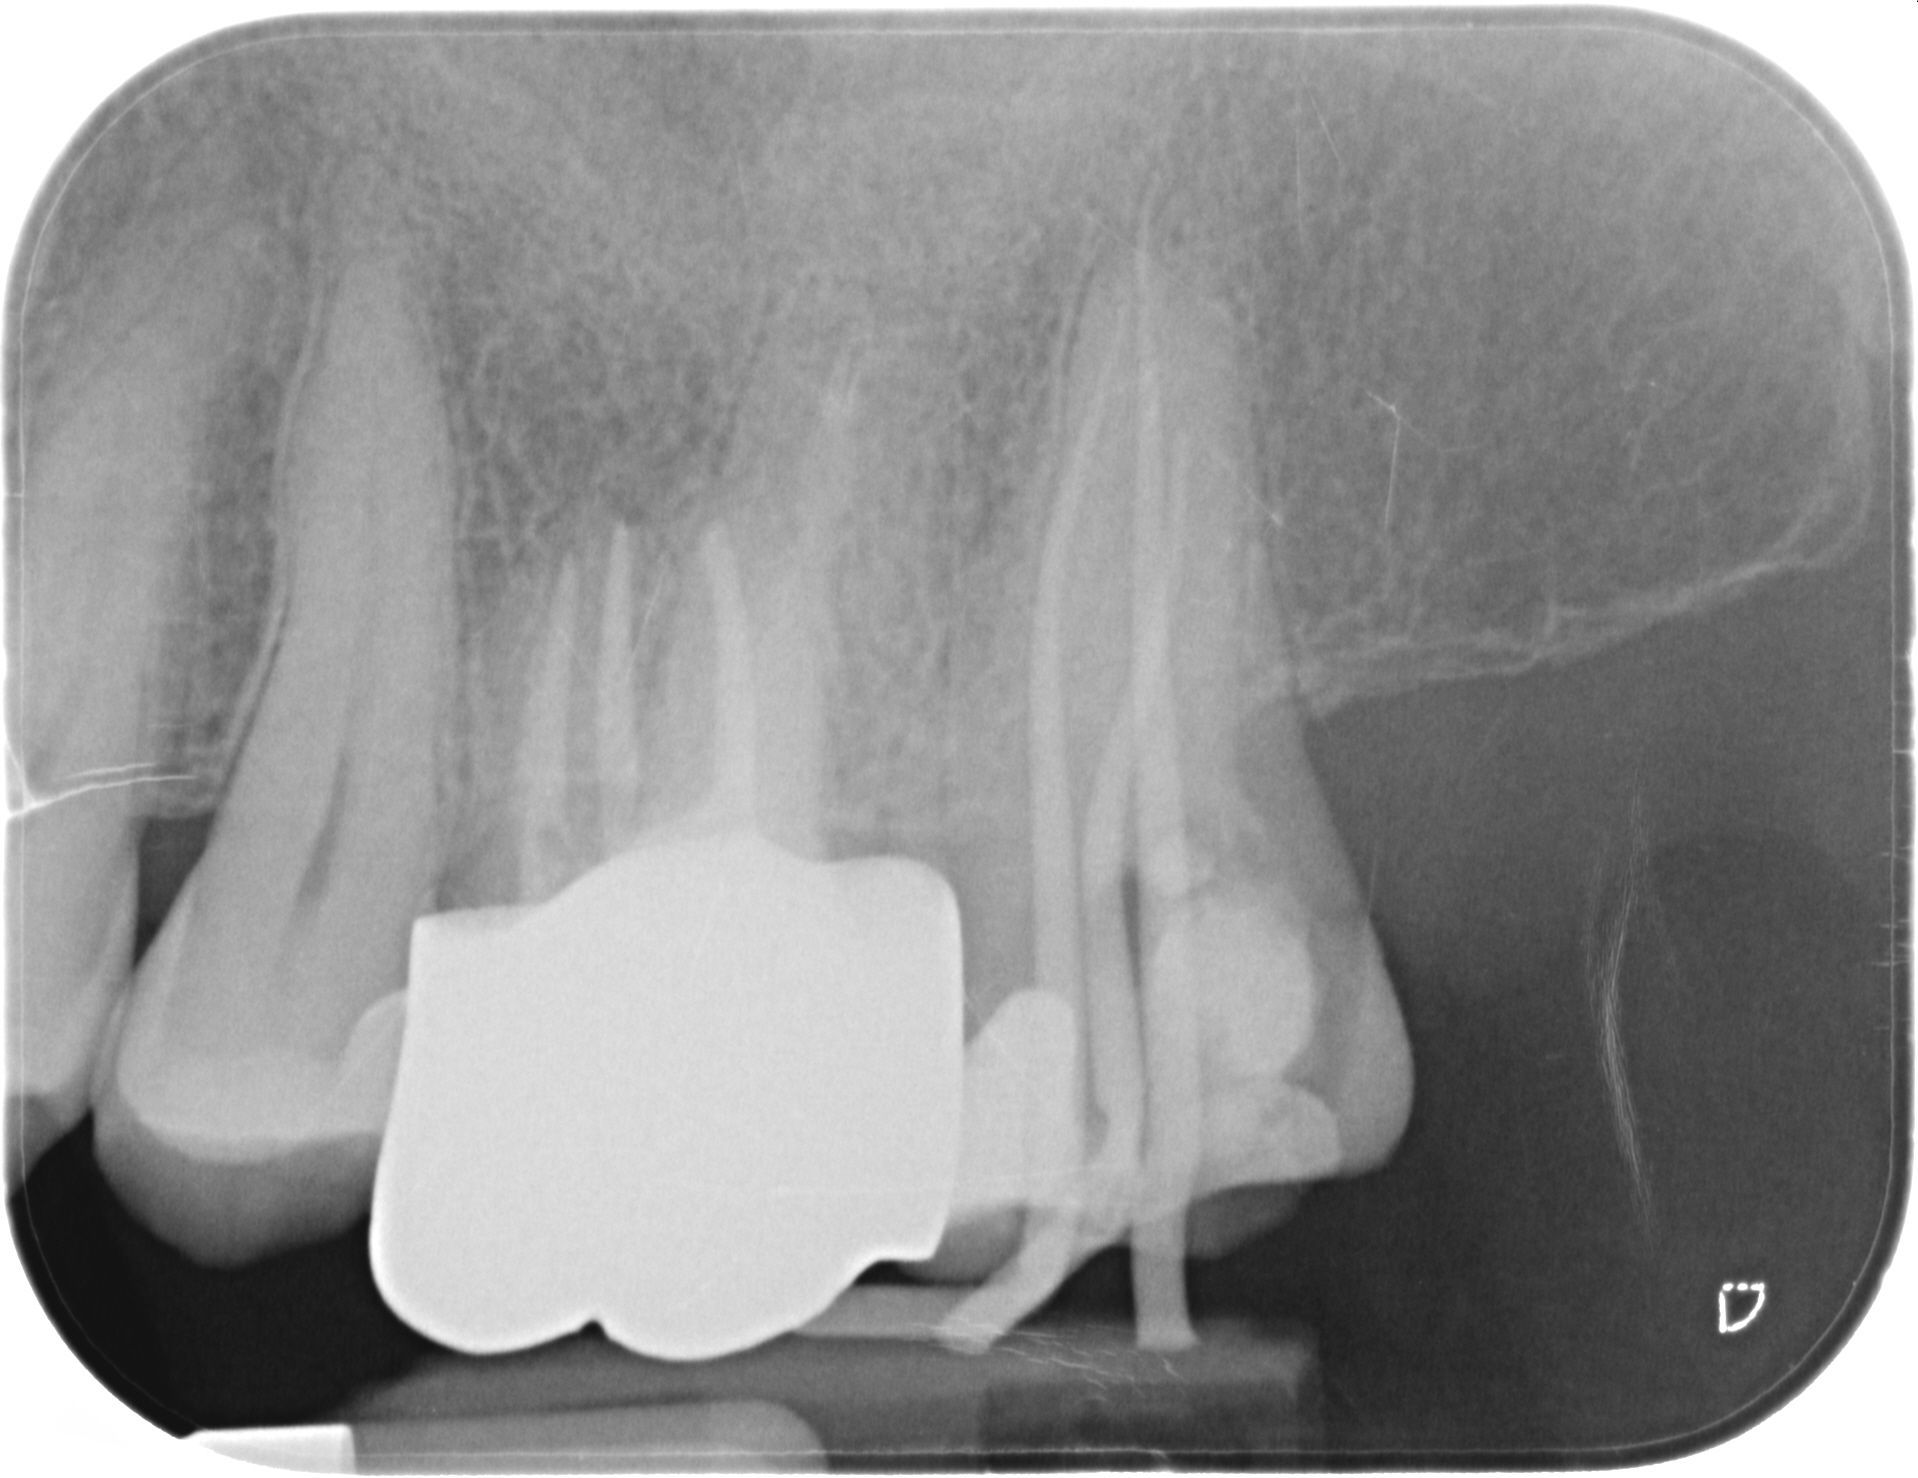

L'endodonzia è la branca dell'odontoiatria che si occupa della cura dell'endodonto ovvero dello spazio all'interno del dente che contiene la polpa dentaria costituita da componente cellulare, vasi e nervi. Il fine è quello di eliminare le patologie della polpa, siano esse acute o croniche, e/o quelle derivanti dalla stessa.

In questo studio per eseguire le terapie endodontiche si utilizza strumentazione rotante.

Normalmente si esegue anestesia locale e si isola il campo operatorio con la diga di gomma. Le terapie endodontiche sono eseguite dalla Dr.ssa Elena Alciato laureata in odontoiatria e protesi dentaria e abilitata all'esercizio della professione presso l'Università di Pavia nell'anno 1997.